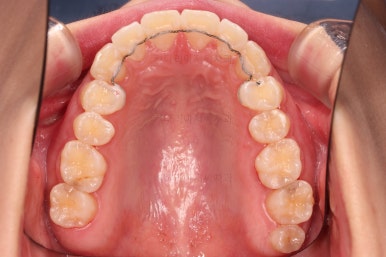

초진 시 입안의 모습입니다.

어금니 쪽은 약간 삐뚤긴 하지만 꼭 교정해야 할 정도는 아니고, 불편감 없이 비교적 잘 맞물리는 상태였습니다.

다만, 앞니ㅉㄱ이 공간이 부족해서 중간 치아들이 많이 회전되어있는데, 이를 환자분들의 표현에 따르면 "나비치아" 라고 부릅니다.

위아래 중간 앞니가 모두 나비치아처럼 되어있고요.

윗니가 아랫니보다 앞쪽으로 나와 있는 모습에 아래앞니가 윗니쪽으로 깊숙이 올라간 "과개교합" 양상을 보였습니다.